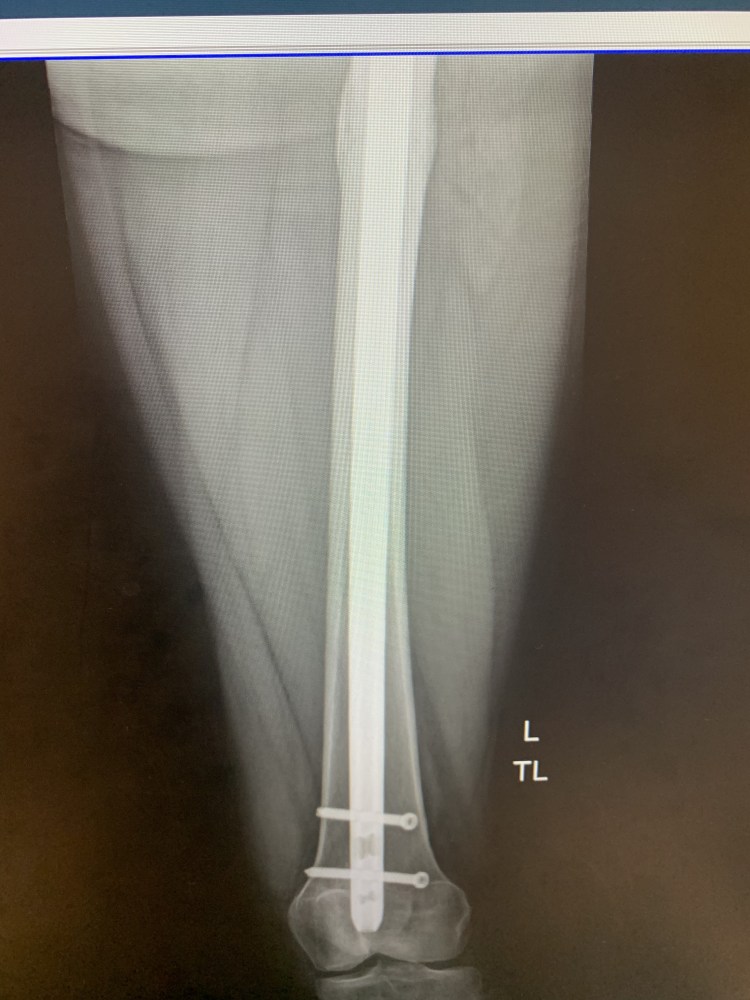

HOWEVER, I saw my surgeon yesterday (7/26) and it turns out it is the screws causing soft tissue pain! Easy fix!! He did warn me of this back when I had the surgery.

Therefore, I am scheduled to have the screws removed in about 3 weeks

(August 17th), as they are no longer necessary since my femur fracture is healing well. It is a minor procedure.